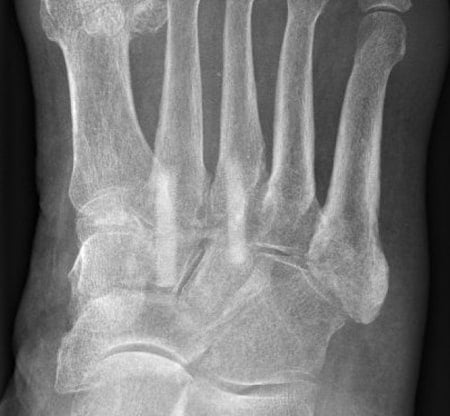

Röntgenbild präoperativ

Im Kontrollröntgen zeigt sich die Arthrose deutlich.